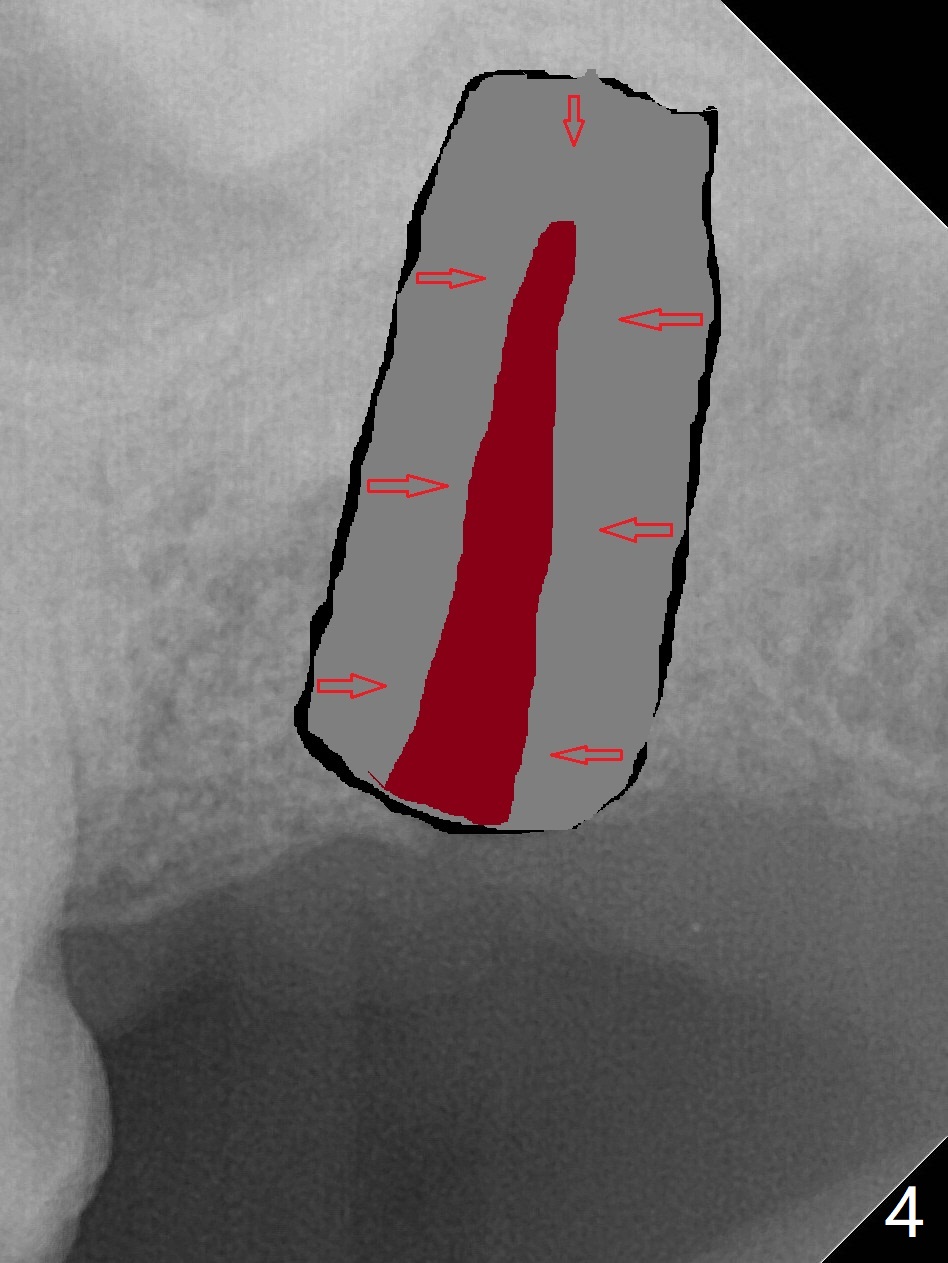

59岁男一年前因15号牙植牙周围炎去除牙冠和基台,植骨(图一:*(其实是第二次为周围炎植骨)),缝合。之后局部疼痛没有完全消失,准备再次手术(切开),如果螺纹暴露少,再次植骨。否则拔除植体(图二:黑色,手术探查的确不能挽救植体),之后有两个选择植骨(图三:灰色)或者即刻再次种植。由于原来植体比较粗(骨水平;6x12毫米),利用6(内径)/7(外径)毫米trephine drill和牙挺除去植体,留下相当大缺损(图二),植骨后(图三),位于缺损中间的骨粉(图四:棕色)可能因血供(红箭头)不足而愈合不佳。因此即刻重新种植显得有优势(图五(软组织水平植体,螺纹在自身骨(native bone)下)),让身体不必太辛苦(成骨)。放置5x5毫米基台目的是为树脂敷料提供固定点,以防PRF膜和缝线不能挽留粘性骨粉(*)。术后一个月撤除树脂敷料,伤口愈合正常(图六)。准备一个月后,制作临时牙冠。术后4个月取出5x5毫米基台,准备放置6x5毫米基台(图七),下面软组织水平植体没有疼痛或者松动,螺纹被骨粉或者再生骨质覆盖(^)。